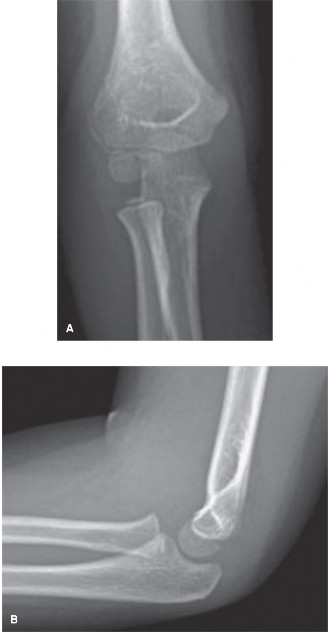

CASE 38 The patient is a 5-year-old boy who is referred into the emergency depa…